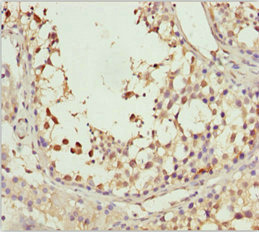

應用范圍:ELISA, IHC

Application Recommended Dilution IHC 1:20-1:200 -